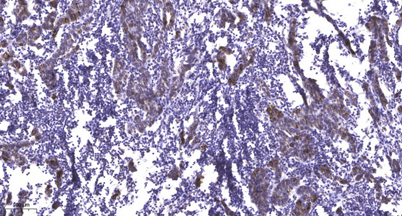

Recomended Dilution Immunohistochemistry: 1/100 - 1/300. ELISA: 1/10000. Not yet tested in other applications.